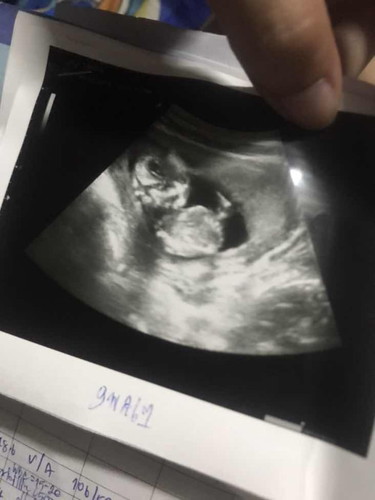

ท้องแรก 14 สัปดาห์ ป้าหมอบอกน้องตัวใหญ่มาก💖👶🏻🫶🏻

14 สัปดาห์ คนไหนรู้เพศแล้วมั่งคะ มาแชร์หน่อยน๊าา